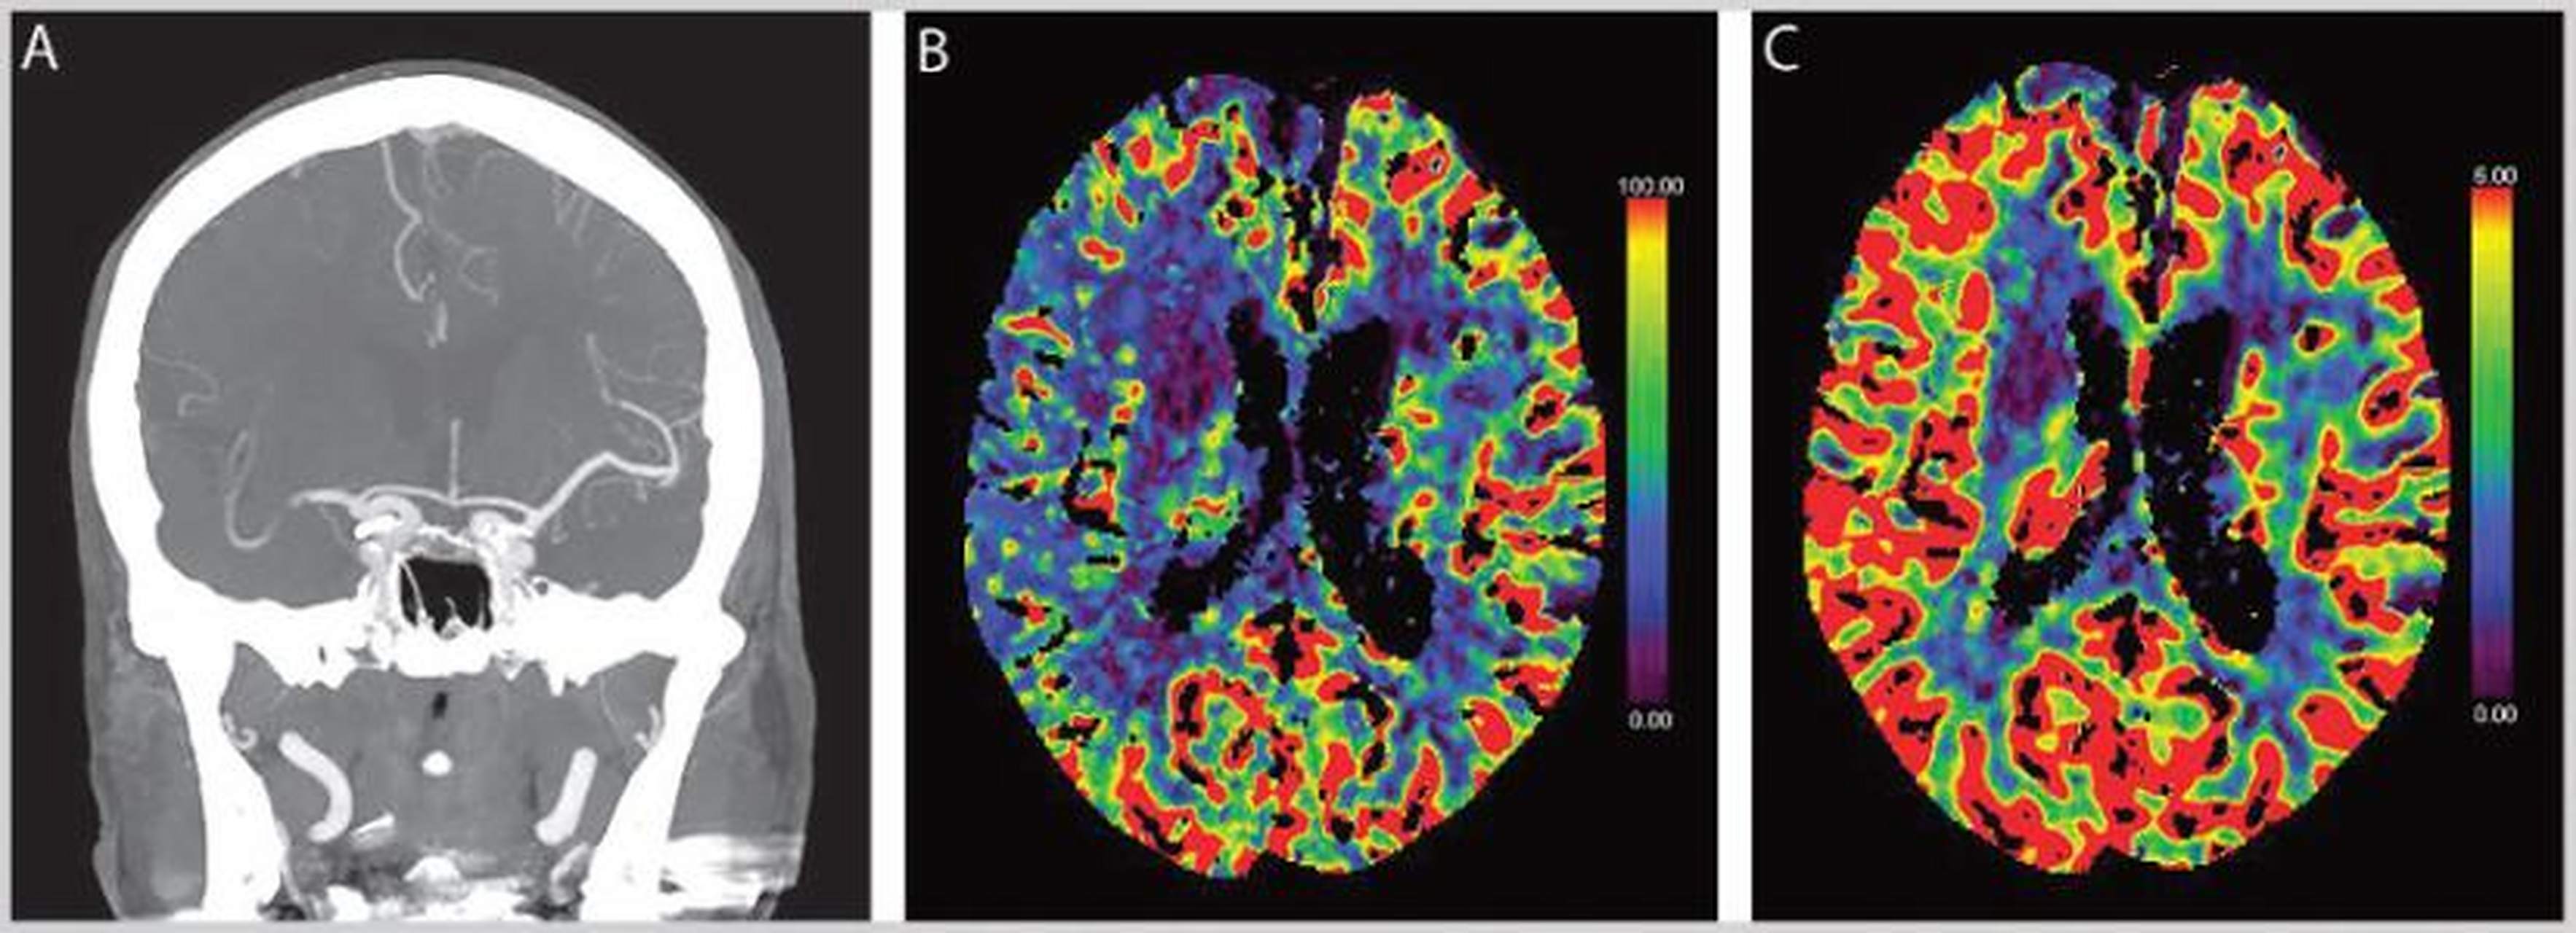

顺时针方向依次:脑血流量cbf,达峰时间ttp,平均通过时间mtt,脑血